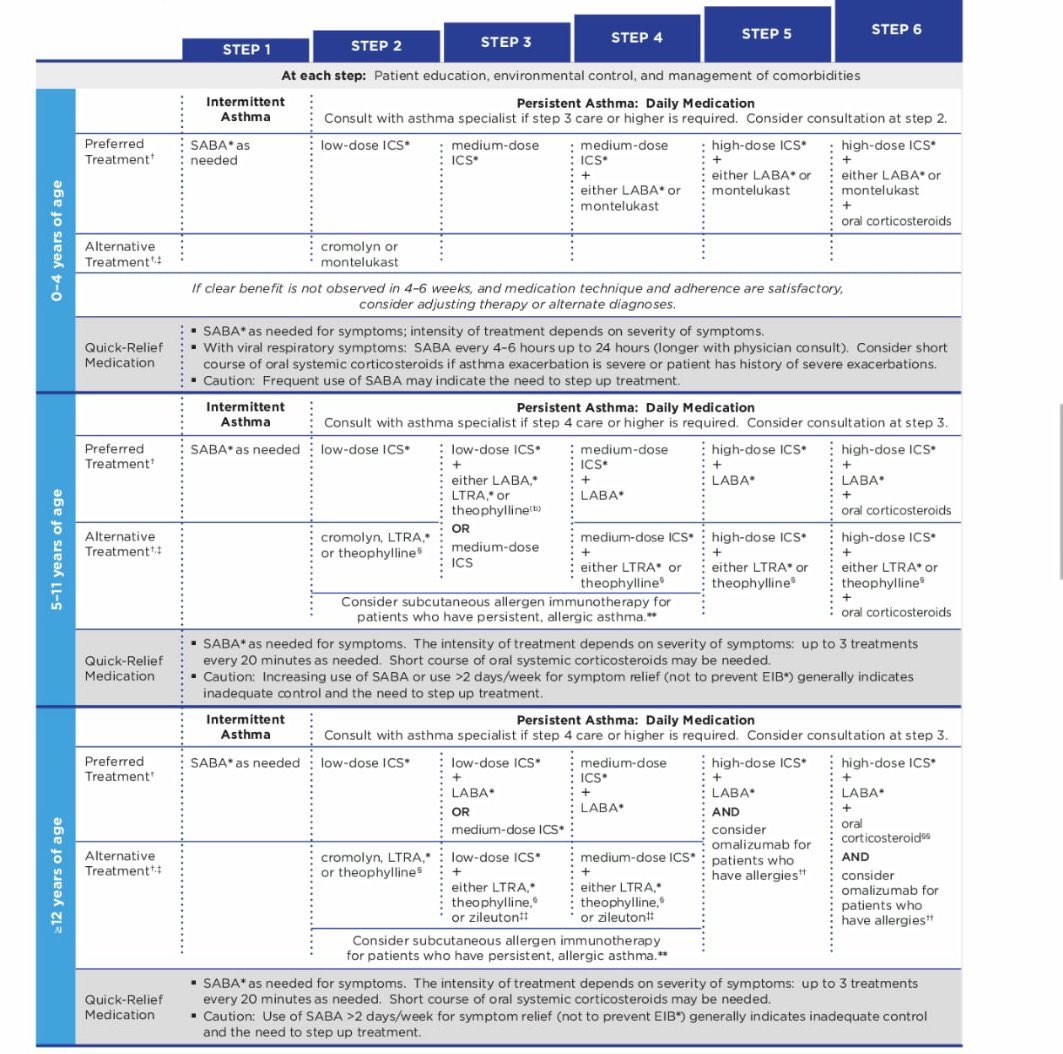

8_ايش هي الخطه العلاجيه بالترتيب للPediatrics و الadult ؟

🔴ثامنًا: ايش هي الخطه العلاجيه بالترتيب :

بعد مايرد طبيعي تبدأ الخطه كالتالي

يلا نبدأ خطة المزمن #chronic /

if symptom less than 2 days per week Will be #intermittent(before mild) & Give him: #step 1

#Step 1: SABA (short acting beta agonist )PRN

if symptom less than 2 days per week Will be #intermittent(before mild) & Give him: #step 1

#Step 1: SABA (short acting beta agonist )PRN

يعني احد ادوية SABA يعني عند اللزوم

🔴 تاسعا : ايش الgiudeline الي نستخدمها كمرجع للخطط العلاجيه في asthma ؟

3_NAEPP guideline